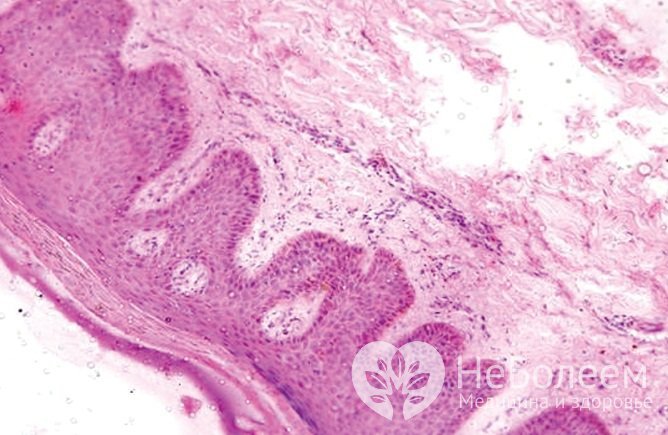

Красный плоский лишай дебютирует появлением папул розовато-фиолетового цвета с блестящей поверхностью. Элементы сыпи локализуются на туловище, конечностях, слизистых оболочках полости рта и наружных половых органов, их появление может сопровождаться зудом и болезненностью. В ряде случаев поражение слизистых оболочек возникает изолированно.